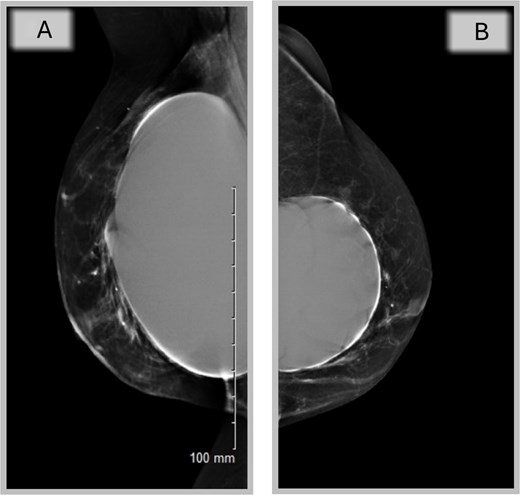

A completion mastectomy was recommended to facilitate whole breast reconstruction (WBR), but oncological multidisciplinary team (MDT) revealed no indication (Fig. 4A and B).

Mammography of the two breasts shows asymmetrical augmentation of the two breasts with no evidence of implant rupture or parenchymal abnormality supporting oncological MDT’s recommendation.